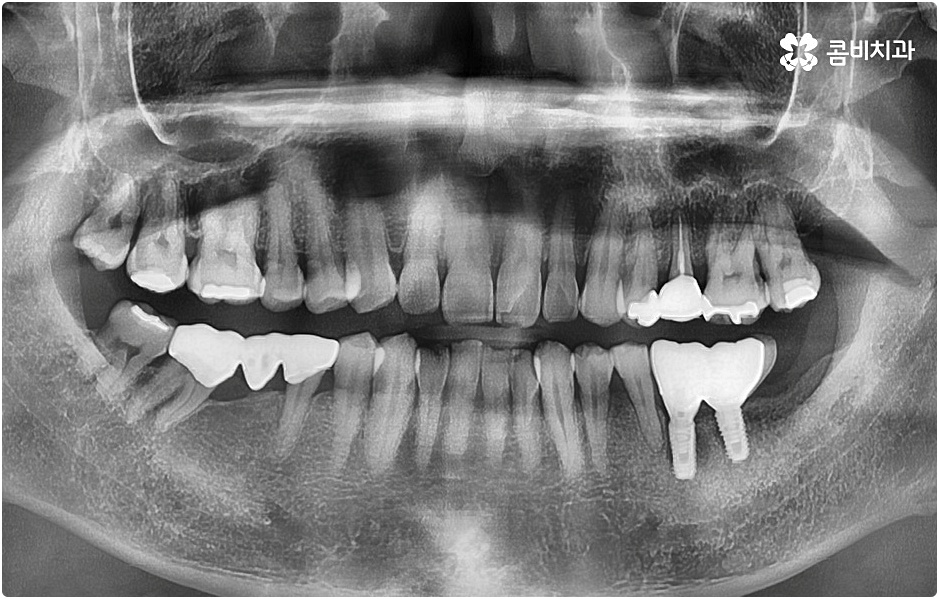

즉시 임플란트 시술은 시간적인 부담이나 수술 과정에서의 불편 등을 줄여줄 수 있는 장점을 가지고 있으며 특히 앞니 등 입을 벌렸을 때 바로 보이는 치아에 손상을 입으신 분들의 경우 심미적인 이유로도 보다 빠른 수복을 원하시기 때문에 이에 대해 문의를 주시는 분들이 많이 있어요. 20대임플란트 시술을 받아야 하는 상황이라면 대인 관계가 넓어지고 사회 활동이 활발해지는 시기인 만큼 더욱 더 치아의 공백을 빠르게 대체할 수 있기를 희망하실 거예요.

그러나 언급했던 것처럼 잇몸뼈 상태에 대해서 먼저 체크해 봐야 하기 때문에 누구나 받을 수 있는 치료 과정은 아니라는 점을 분명히 알아두실 필요가 있습니다. 이렇게 잇몸뼈를 보충해야 하는 상황 뿐 아니라 충치 또는 치주 질환을 먼저 깨끗하게 치료해야 하는 상황, 상악동까지의 거리가 너무 짧아서 거상술을 통해 혹시 모를 천공과 염증을 방지해야 하는 상황 등 여러 가지 선치료가 필요한 케이스들이 있을 수 있기 때문에 먼저 환자분들의 상황을 자세하게 파악하기 위해서 꼼꼼한 검진을 해 볼 필요가 있으므로 3D CT 등 정밀 검진 장비 보유 여부가 필수적이라고 말씀드린 거예요.

환자분들의 상황에 따라 즉시 임플란트 시술이 가능하지 않은 경우라고 해도 만약 본원과 같이 치과 내부에 자체 기공소를 갖추고 있다면 기간 단축은 물론이고 보다 정교하고 섬세한 보철물 제작 및 혹시 모를 수리와 수정 역시 빠르고 원활하게 이루어진다는 점에서 환자분들의 부담과 불편이 크게 줄어들 테니 너무 걱정하실 필요는 없을 거예요. 또한 임플란트 치아의 경우 정기 검진을 꼬박꼬박 받고 스케일링 치료 등을 통해 주변 잇몸 건강을 철저하게 돌본다면 거의 반영구적으로도 사용할 수 있으니 임플란트 시술 후 일상 생활 속에서 이를 건강하게 유지 관리할 수 있도록 식습관 및 생활 습관, 칫솔질 등에 주의하면서 내원 주기를 잘 맞춰주시길 당부드리고 있습니다.